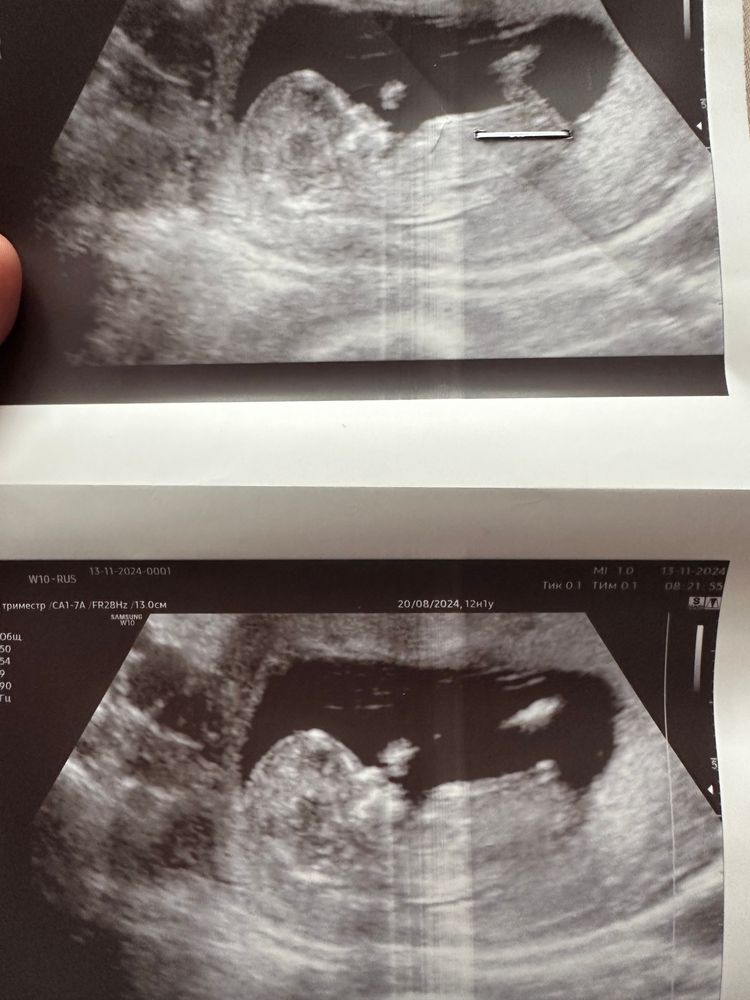

1 скрининг ,кто -нибудь разбирается в поле ребёнка ?)

По мне на девочку похоже очень.

На первом скрининге вам даже узист не скажет кто у вас. Только предположить может и то не каждый. Там ещё ничего не понятно

Анна, почему-то я уверенна, что если мальчик, то на первом скринге узистка говорит 100% А если девочка, то на первом почему-то легко спутать с мальчиком

Зай, да мне сына на 1-ом сразу сказали и не ошиблись)

Qazplm, у вас больше вроде на девчулю

Подскажите пожалуйста, к вам прикрепление по передней стенке или по задней?

Екатерина Ткаченко, по передней